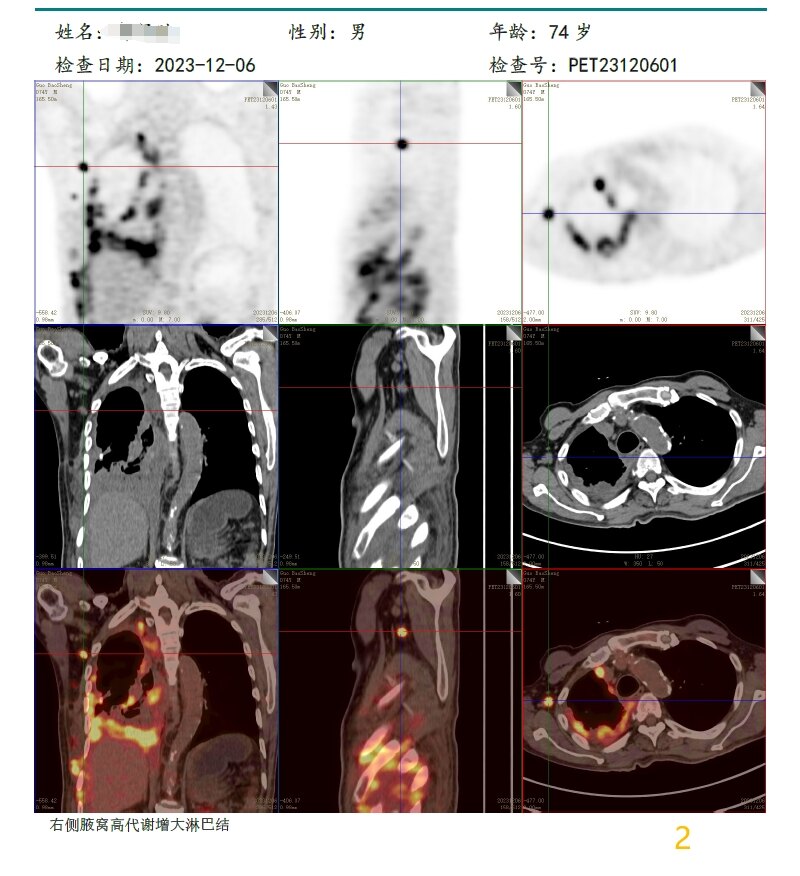

放疗前PET/CT(2023-12-06):

2

病变层面: